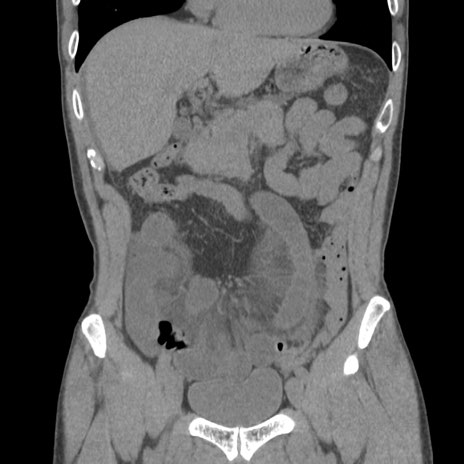

症例56 CT(冠状断像)

脂肪ウインドウ

横断像